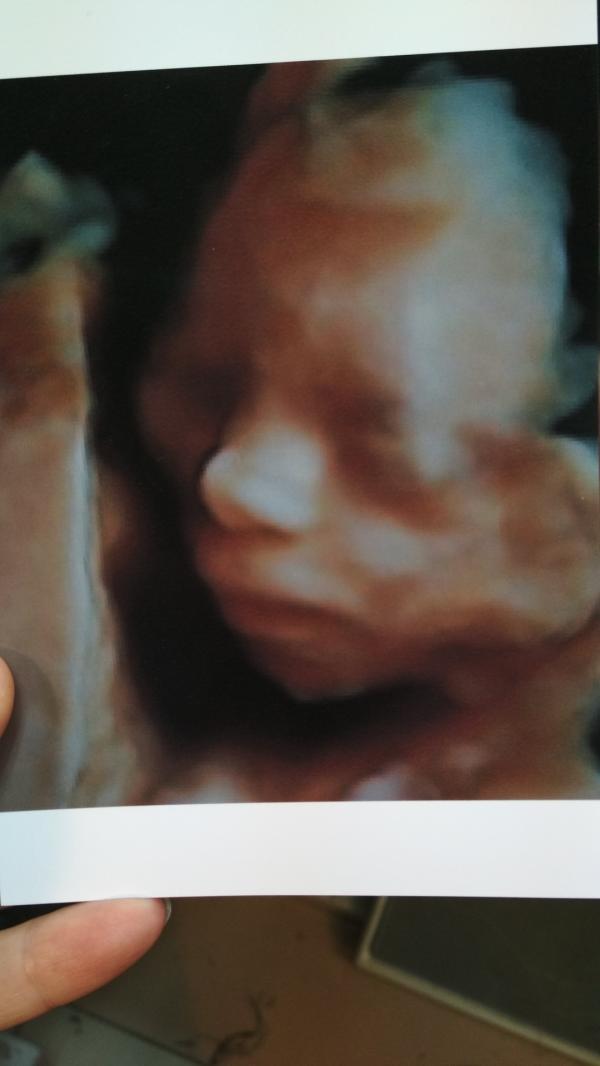

Второй скрининг пройден, наша долгожданная дочурка: эмоции и впечатления будущей мамы

Вот и у нас прошёл второй скрининг.

Моя долгожданная пуговичка 🥰

Уже всем сердцем любимая дочурка.